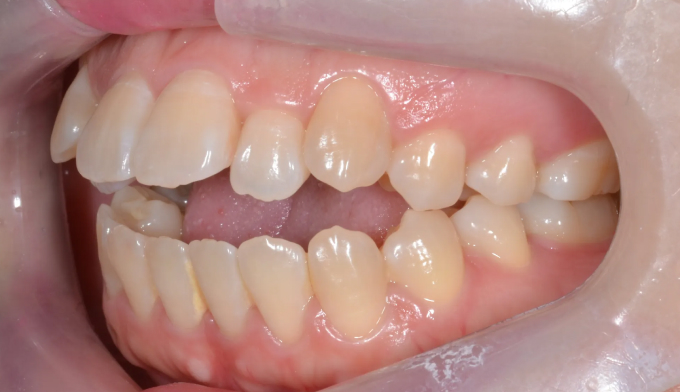

돌출입과 개방교합이 동시에 있는 경우에는 발치교정을 통해 앞니를 넣어주면 개방교합이 쉽게 개선됩니다. 이때 주의할점은 미소시 치아의 노출정도입니다. 또한 개방교합의 경우에는 재발 경향이 높기 때문에 주기적인 경과관찰이 필요하며 최종위치에 안정적으로 치아가 위치해있다고 판단이 들었을 때 교정치료를 종료하여야 합니다.

총 교정기간은 25개월입니다.